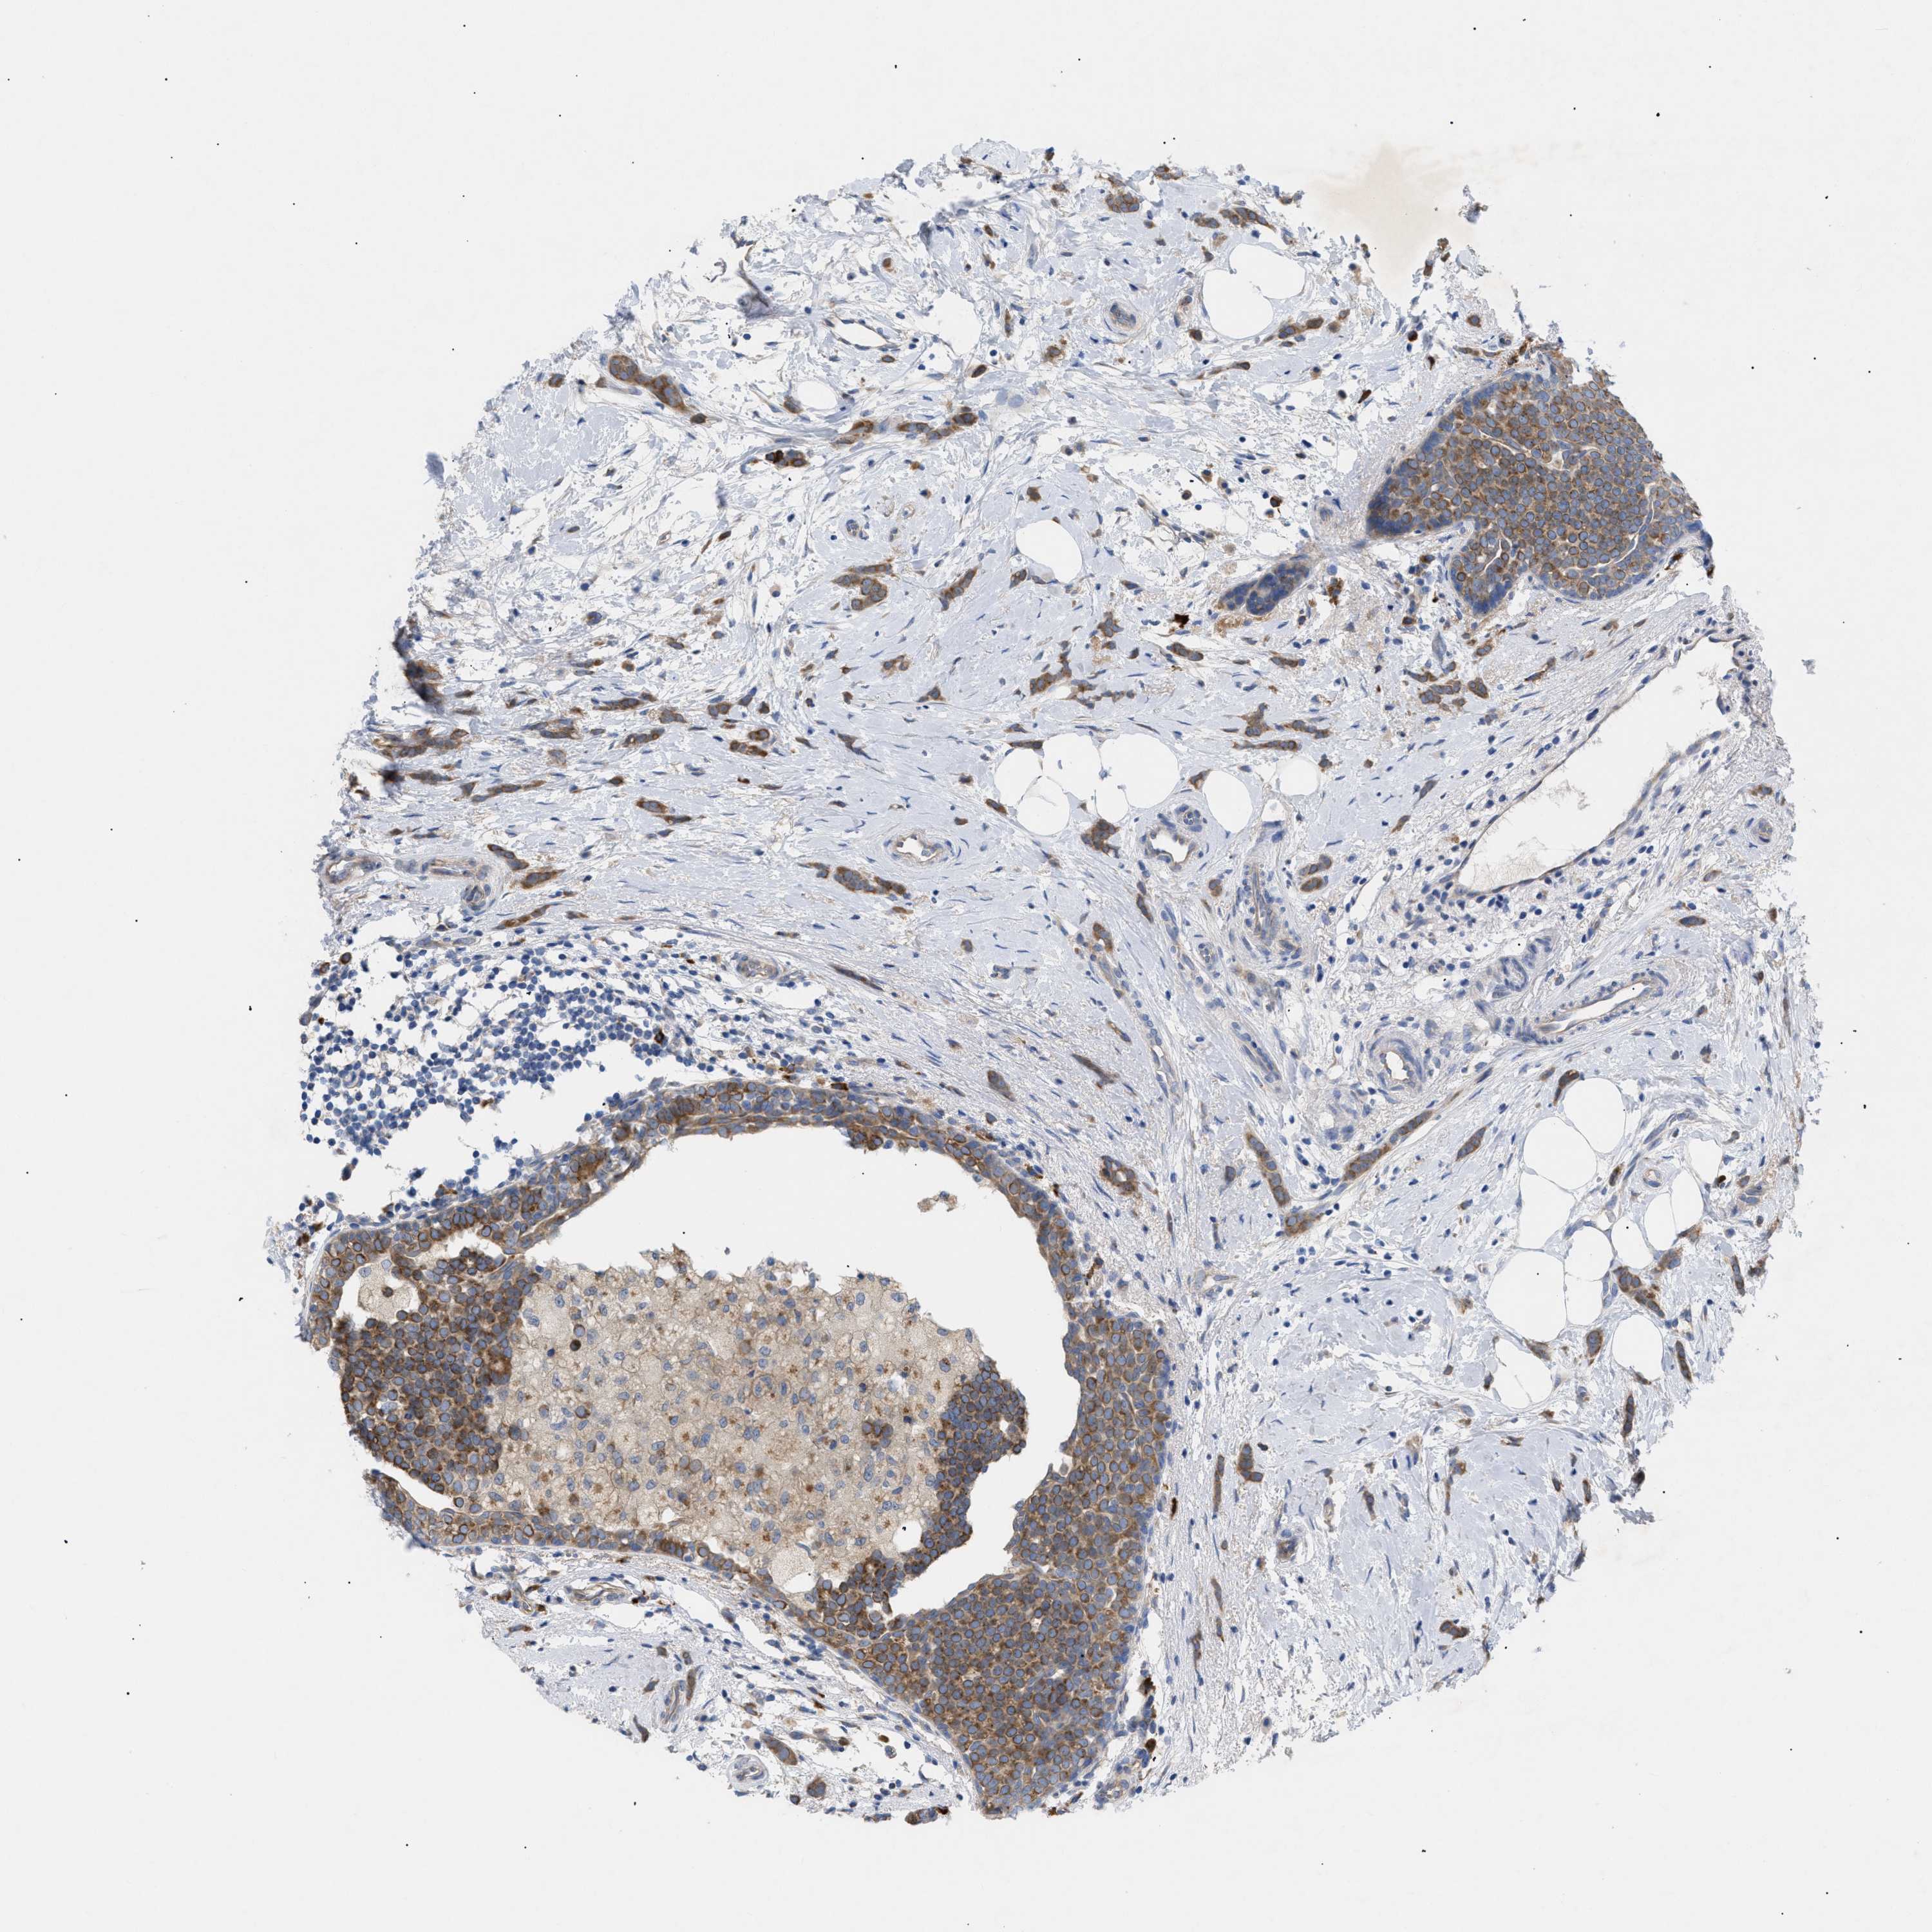

CANCER BREAST CANCER Show tissue menu

BRCA TCGA BRCA VALIDATION PROTEIN EXPRESSION